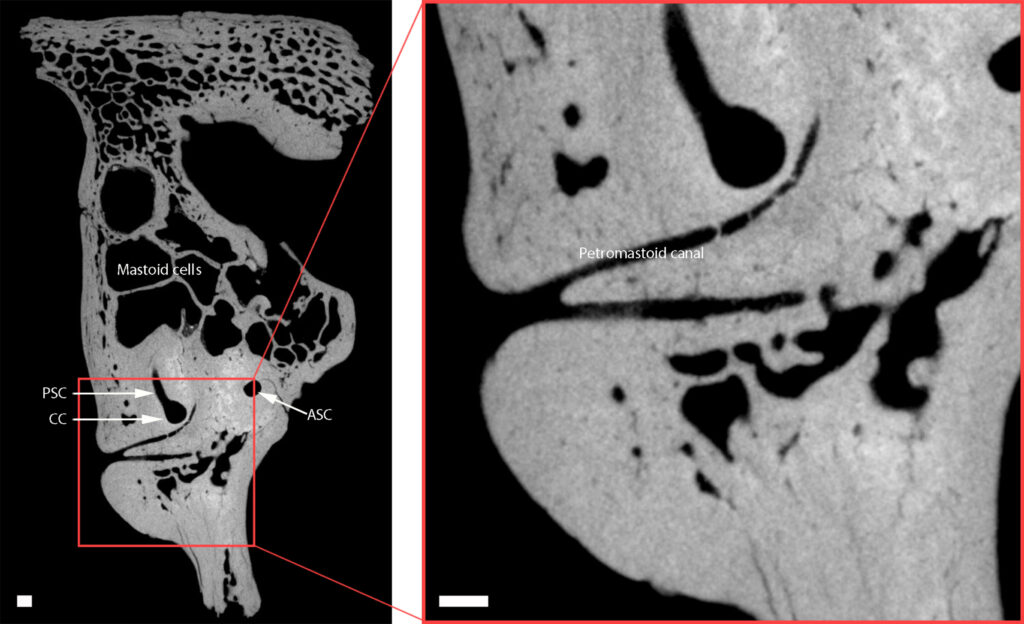

The conclusions drawn from this discovery are grounded in detailed and rigorous scientific analysis, combining modern technology with careful interpretation of ancient remains. Researchers focused on the child’s temporal bone, a critical part of the skull that houses structures of the inner ear. This region plays a key role in balance and hearing, and abnormalities here can provide important clues about underlying conditions.

CC, common crus; PSC, posterior semicircular canal; ASC, anterior semicircular canal. Scale bar, 1 mm.

Credit: Conde-Valverde et al. (2024)